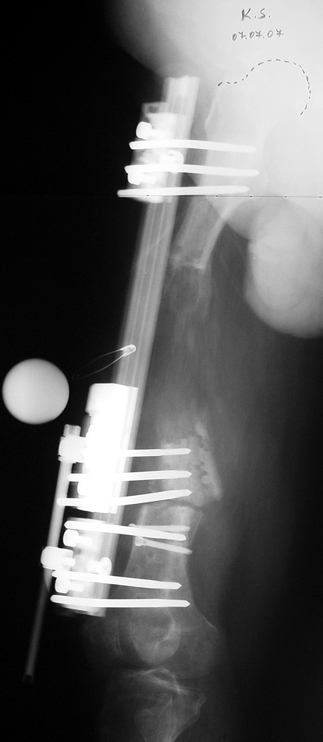

Appropriate radical debridement necessitates excision of all necrotic bone and soft tissues, and frequently causes instability at the involved extremity. The remaining bone and soft tissue defect has to be fixed and reconstructed. The distraction osteogenesis method of Ilizarov is used successfully for achievement of union, correction of the deformity, elimination of limb length inequality and reconstruction of segmental bone defects.

The duration of external fixation (external fixation index) depends on the amount of distraction required, and the extremity is prone to complications during this period. After the distraction phase is completed, the external fixator remains in place during the consolidation phase, which lasts twice as long as the distraction phase; but this period is hardly tolerated. If the external fixator is removed before sufficient consolidation is achieved, fractures, deformity and shortness will be the result. In our department, ‘lenghthening over nail’ method is used in order to decrease the external fixation index and increase patient comfort and activity level. In this method, the intramedullary nail is statically locked after the completion of the distraction phase, and external fixator is removed. The extremity is stabilized by the intramedullary nail during consolidation phase. In this way, complications due to long external fixation index or early removal of the external fixator are avoided.

Case 3